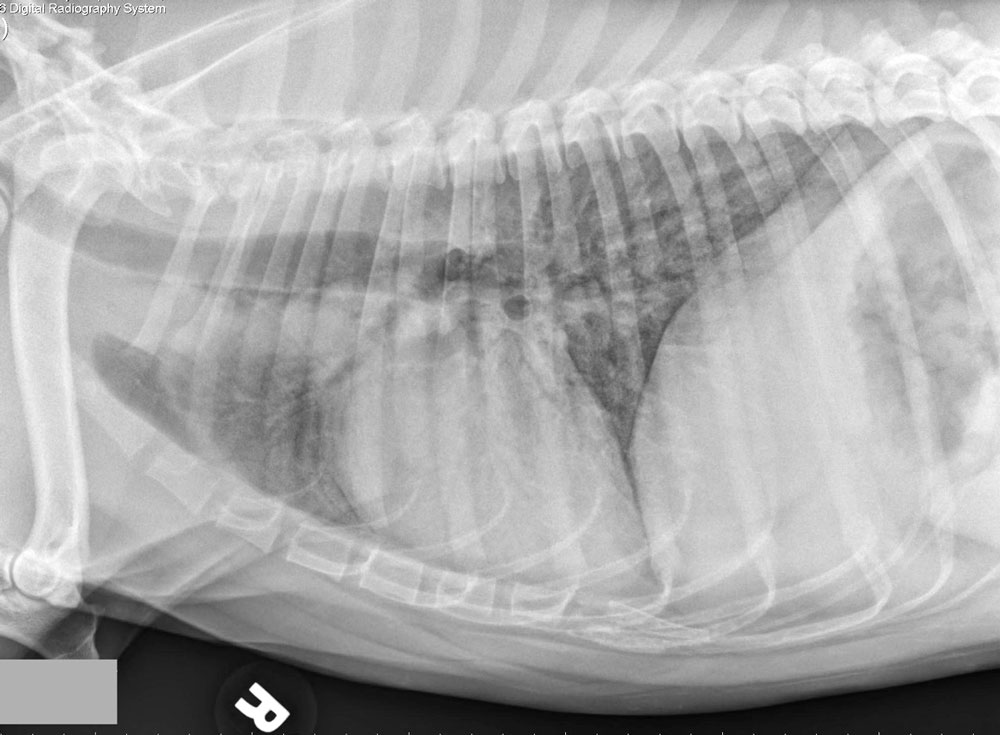

Для диагностики помимо клинического осмотра и аускультации (выслушивания при помощи фонендоскопа дыхательных шумов) используют рентгенографическое обследование грудной клетки. В критических ситуациях, когда есть существенная угроза жизни, все диагностические мероприятия проводятся только после стабилизации пациента.